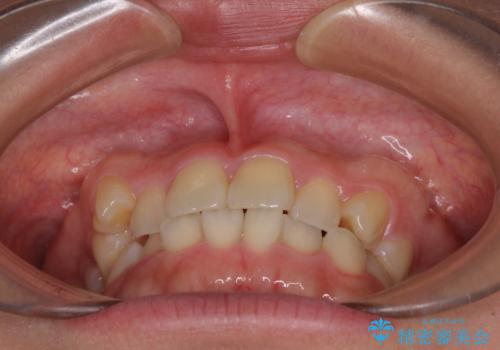

八重歯を治す 非抜歯のワイヤー矯正治療

- 左右の八重歯を気にして来院された患者様です。

ワイヤー装置でもマウスピースでも対応可能な歯列でしたが、マウスピース矯正は自己管理が煩わしいとのことでワイヤー矯正を選択されました。

八重歯である犬歯は歯根が長いため、上顎前歯が出っ歯になるリスクがあるため、必要に応じてアンカースクリューを用いて奥歯を後方に移動させる可能性をお伝えしました。